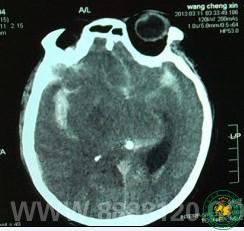

我科成功急诊夹闭颅内动脉瘤一例

我科成功急诊夹闭颅内动脉瘤一例3905